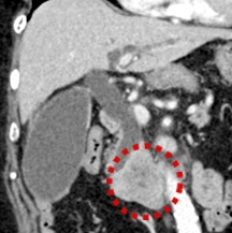

CT画像(他院にて施行)